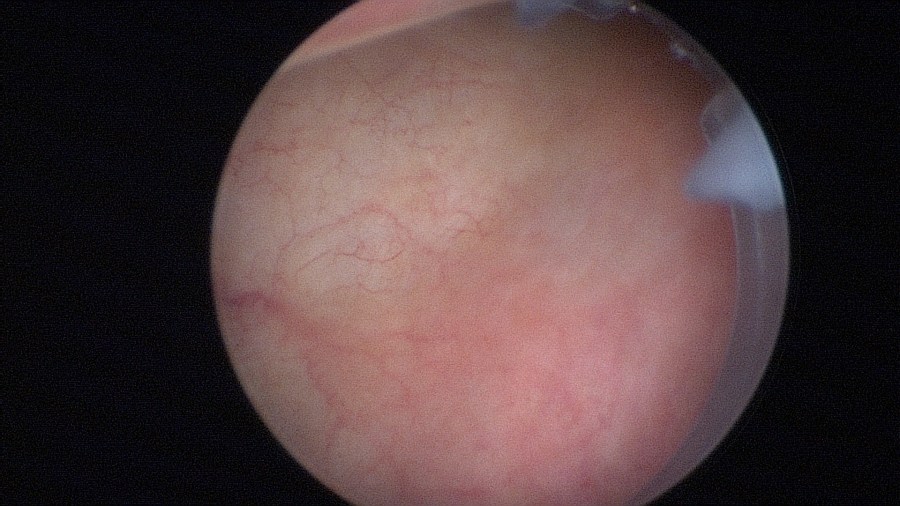

Beginn with a thorough cystoscopy. Patients that have incontinence recurrence should be examined for sling or even suture erosion. Watch out for tumors or stones.

Documentation of the right ureteral orifice.

Documentation of the left ureteral orifice.